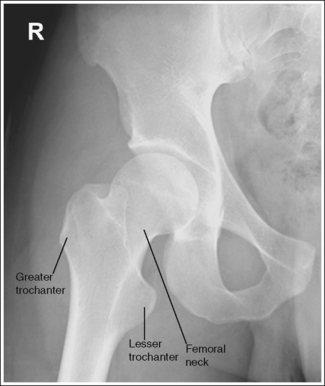

The femoral neck is demonstrated without foreshortening, the greater trochanter is in profile laterally, and the lesser trochanter is superimposed by the femoral neck.

• Accurate leg positioning. To demonstrate an AP hip projection with the femoral neck shown without foreshortening and the greater trochanter in profile, the patient's leg should be internally rotated until the foot is angled 15 to 20 degrees from vertical and the femoral epicondyles are positioned parallel with the imaging table (Figure 7-4; see Figure 7-1). A sandbag or tape may be needed to help the patient maintain this internal leg rotation.

The femoral head or neck is at the center of the exposure field. The acetabulum, greater and lesser trochanters, femoral head and neck, and half of the sacrum, coccyx, and symphysis pubis are included within the collimated field. Any orthopedic apparatus located at the hip are included in their entirety.

• A perpendicular central ray is centered 1.5 inches (4 cm) distal to the midpoint of a line connecting the ASIS and superior symphysis pubis, to center the hip joint in the center of the exposure field, and a perpendicular central ray is centered 2.5 inches (6.25 cm) distal to the midpoint of a line connecting the ASIS and superior symphysis pubis to place the femoral neck in the center of the exposure field (Figure 7-6). Center the IR to the central ray and open the longitudinal collimation enough to include the ASIS and any hip orthopedic apparatus. Transversely collimate to the patient's midsagittal plane and within 0.5 inch (1.25 cm) of the lateral hip skin line. Including half of the sacrum, coccyx, and symphysis pubis within the exposure field provides a way to evaluate pelvic rotation.

• A 10- × 12-inch (24- × 30-cm) IR placed lengthwise should be adequate to include all the required anatomic structures. A larger IR and lower centering point may be necessary to include hip orthopedic apparatus (Figure 7-7).